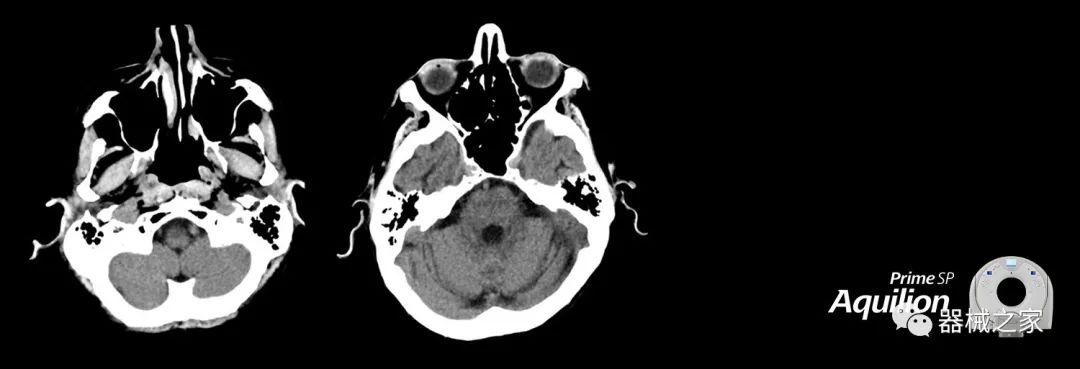

在以患者為中心的放射腫瘤學(xué)領(lǐng)域,計算機斷層掃描(CT)的可訪(fǎng)問(wèn)性,可重復性和靈活性至關(guān)重要。為了建立這些價(jià)值,佳能醫療系統美國公司現在正在擴大其放射腫瘤學(xué)CT模擬產(chǎn)品,包括Aquilion Prime SP和Aquilion Lightning 80高級CT系統。除了Aquilion LB之外,Aquilion Prime SP和Aquilion Lightning 80現在還包括放射治療(RT)選項,可為腫瘤學(xué)規劃提供高質(zhì)量的CT成像和精密工具。

擴展視野(EFOV)可以看到更多的解剖結構。Aquilion LB采用85 cm EFOV,而Aquilion Prime SP和Aquilion Lightning 70采用70 cm EFOV。

Aquilion Prime SP使設施能夠處理具有挑戰性的案例,同時(shí)為員工提供快速,靈活和高效的解決方案。

兩個(gè)CT系統均采用0.5 mm x 80排PUREViSION探測器技術(shù)(可配置并從80-160現場(chǎng)升級),78 cm孔徑,50 cm視野,AIDR(自適應迭代劑量減少)3-D和SEMAR(單個(gè))能量金屬神器減少)技術(shù)。

Aquilion LB專(zhuān)為滿(mǎn)足腫瘤學(xué)挑戰而設計,同時(shí)優(yōu)先考慮患者護理。Aquilion LB的內徑為90 cm,能夠幫助復雜的患者設置并提高患者的舒適度。CT模擬定位可以輕松鏡像放射治療定位,更加自信。該系統采用0.5 mm x 16排(32層)PUREViSION探測器技術(shù),70 cm視野,AIDR 3D和SEMAR技術(shù)。